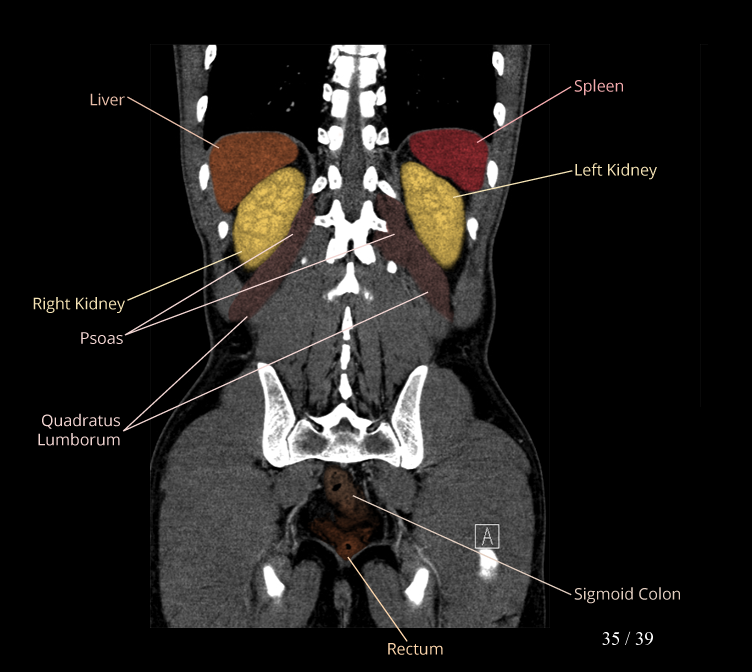

Body

Covers abdominal CT anatomy.